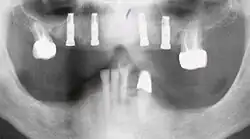

-

OPT mit Zahnlücke Regio 26 und Kugellmessaufnahme mit Kugeldurchmesser 5 mm -

Zahnlücke / Schaltlücke Regio 26 (Seitenansicht) -

Zahnlücke / Schaltlücke Regio 26 (Aufsicht) -

Röntgenbild eines Zahnimplantates in Regio 26 unmittelbar nach internem Sinuslift -